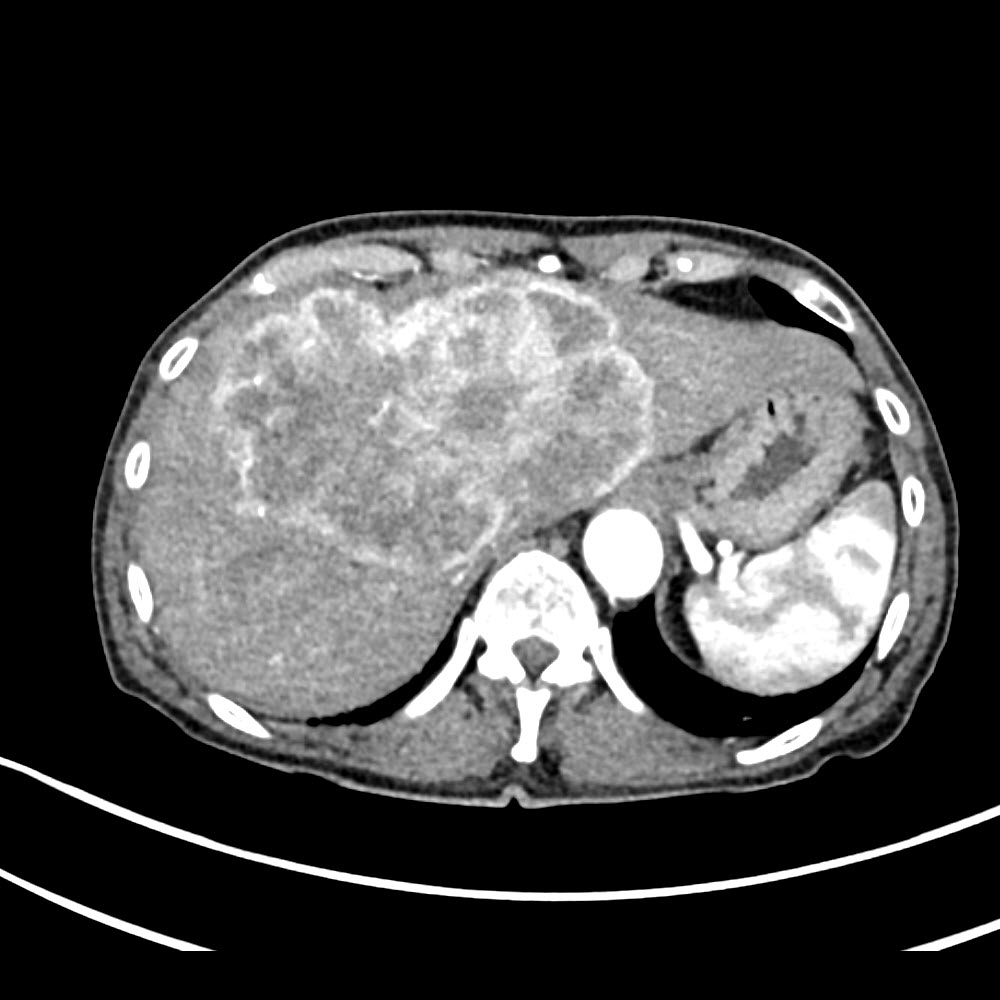

CCC-Darstellung im CT

arterielle und venöse Kontrastmittelphase